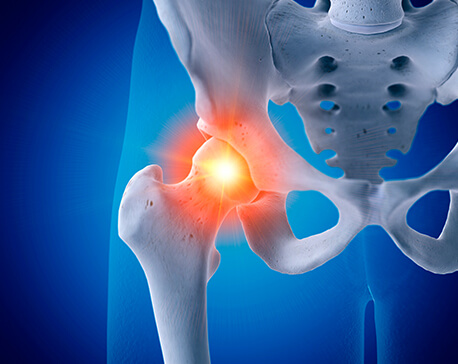

고관절은 흔히 엉덩이 관절이라고 불리며, 골반 쪽에 위치한 공-소켓(ball-and-socket) 형태의 관절입니다. 둥근 모양의 대퇴골두가 오목한 비구(acetabulum)에 맞물려 있어 골반과 허벅지를 연결하는 역할을 합니다.

이 관절은 체중을 지탱하고 보행, 달리기 같은 다리의 움직임을 가능하게 하는 핵심 구조입니다.